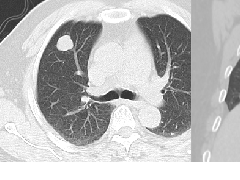

【影像表现】 钡灌肠:直肠与乙状结肠起始部可见不规则充盈缺损(图1箭头),肠管见偏心性狭窄;粘膜皱襞紊乱,纠集(图2、3箭头)。 CT:直肠壁不均匀增厚,见软组织影突入直肠腔内,增强扫描中度强化,周围脂肪间隙欠清楚,直肠后方可见肿大淋巴结(箭头)。肝脏体积增大,肝内密度欠均匀,可见多发弥漫不均匀低密度区,增强扫描病灶显示更加清楚,呈多发结节样低密度影,脾周及胆囊窝周围可见少量液性低密度影。

CT:(1)肠壁增厚,增厚的肠壁黏膜面多明显凹凸不平。(2)腔内肿块影,偏心性,呈分叶状或不规则形,与正常肠壁分界清楚,肿块表面可见小溃疡,呈火山口样。(3)肠腔狭窄,且为非对称性。(4)增强扫描可见较明显异常强化。(5)浆膜及临近器官受侵表现。